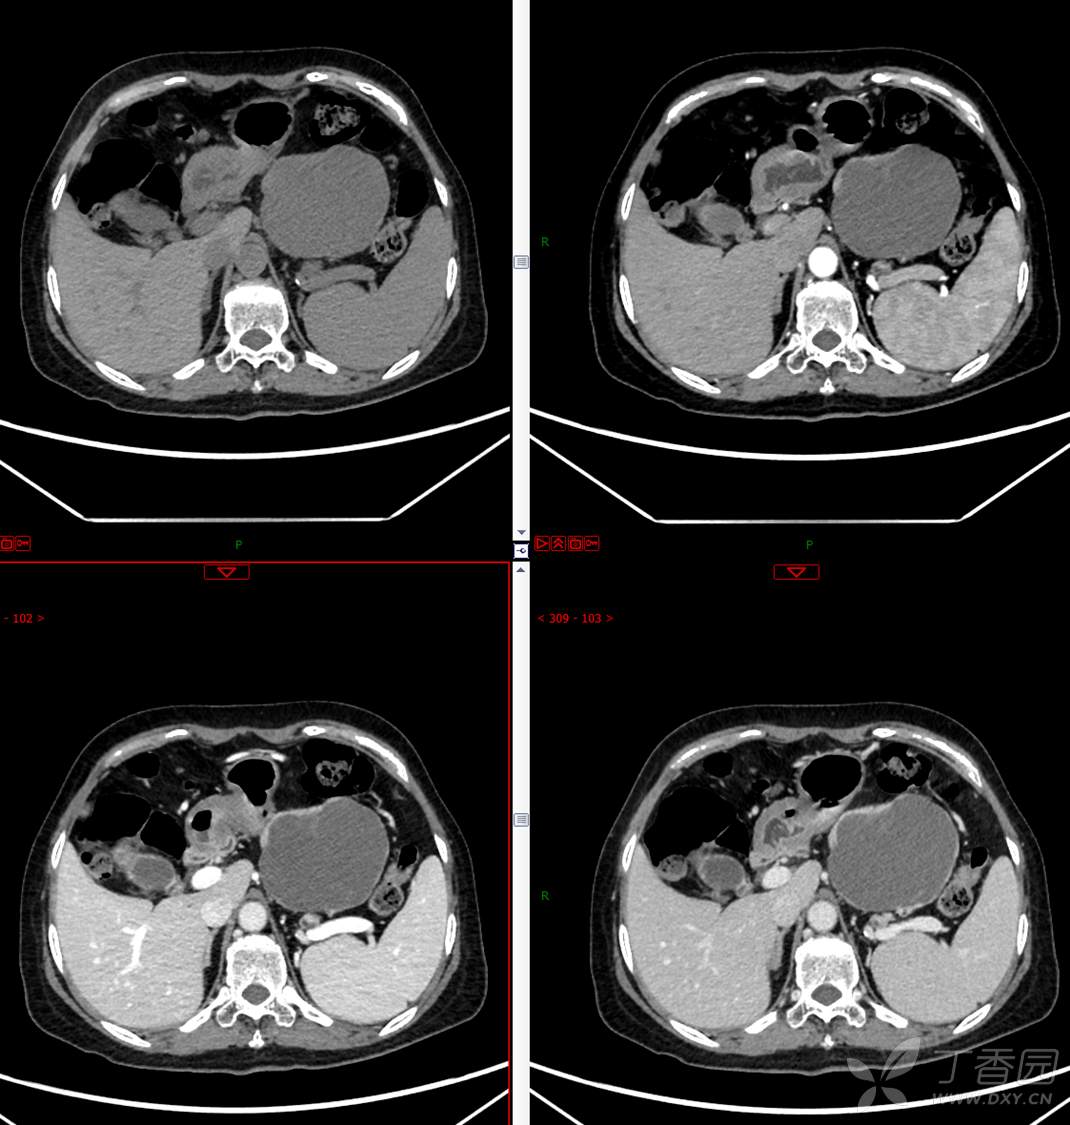

中老年女性胰腺占位,“奶奶瘤”or“妈妈瘤”?请分析领丁当!

主 诉:发现胰腺占位性病变3月

现病史:患者3月前就诊于**市人民医院行腹部增强CT发现胰尾占位性病变,无腹痛、腹胀,无恶心呕吐,无黄疸,无呕血黑便,无胸闷憋气,无寒战高热,未行特殊治疗